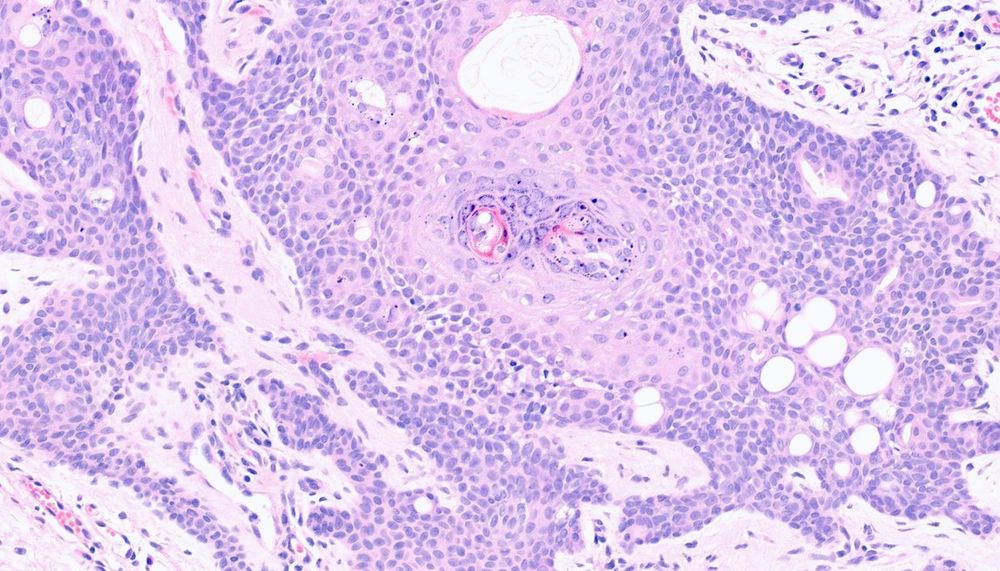

RAC3910 M60s. Dorsal foot warty lesion. ?VW ?SCC.#Dermpath @iyengarish.bsky.social